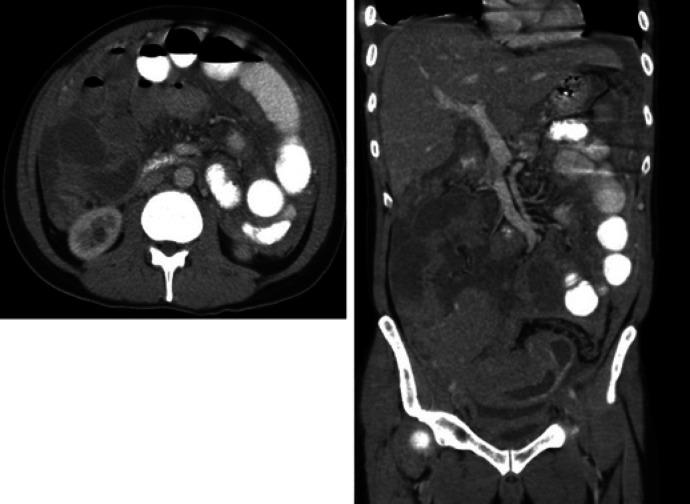

Primary gastrointestinal non-Hodgkin's lymphomas are rare tumors which account for about 0.9% of all gastrointestinal tract tumors. They are usually associated with inflammatory bowel disease, previous radiotherapy, and renal transplantation. We report a case of non-Hodgkin's lymphoma involving the ileocecal region in a 46-year-old gentleman who presented with acute abdominal pain that mandated emergency laparotomy.

原发性胃肠道非霍奇金淋巴瘤是罕见肿瘤,约占所有胃肠道肿瘤的0.9%。它们通常与炎症性肠病、既往放疗及肾移植有关。我们报告一例46岁男性患者,其回盲部发生非霍奇金淋巴瘤,表现为急性腹痛,需行急诊剖腹手术。